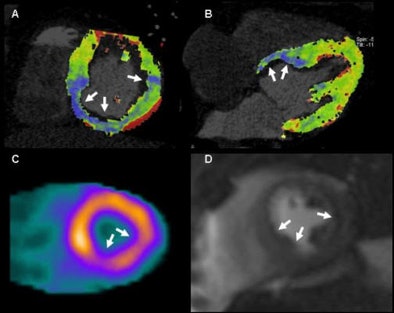

| In a 51-year-old man with suspected coronary artery disease, rest and perfusion CT (above) shows a hypoperfused blue color-coded area inferoseptally, in results that are well-correlated to both SPECT and MRI. In the same patient the results showed delayed contrast enhancement at both CT and MRI, coronary CT angiography revealed calcified plaques in the corresponding coronary artery. |

The researchers examined 30 patients (18 men, 12 women; ages 51-76; mean age, 62 ± 12) using a standardized-protocol triphasic cardiac CT scan that included prospectively electrocardiogram-triggered coronary angiography, dynamic stress myocardial perfusion imaging, and delayed-enhancement imaging. Each patient also underwent stress and rest perfusion MRI, and delayed-enhancement MRI and SPECT, he said.

Scanning with DSCT (Somatom Definition Flash, Siemens Healthcare), the researchers started their imaging sequence three minutes into adenosine stress (regadenoson, 140 µg/kg/min) using a dynamic scanning mode with image acquisition at two automatic table positions and the table shuttling back and forth between the two positions, Weininger explained. Images were acquired at 100 kV and 300 mAs, with a 10% overlap between both acquisition ranges, resulting in 73 mm of anatomic coverage.

The imaging sequence was started four seconds prior to the bolus (50 mL contrast, 50 mL saline chaser at 6 mL/sec flow rate) to ensure a baseline acquisition of noncontrast-enhanced images -- similar to what's done with MRI, Weininger said.

In the quantitative analysis, CT perfusion correctly classified 54 perfusion defects of the 60 identified by MRI, yielding 86% sensitivity and 98% specificity. At the semiquantitative analysis, the group found significant differences in the upslopes of the signal intensity of the time curve between normal and ischemic myocardium of both CT and MRI, Weininger said. In the absolute quantification of myocardial blood flow, CT was again able to differentiate between normal and ischemic myocardium, he said.